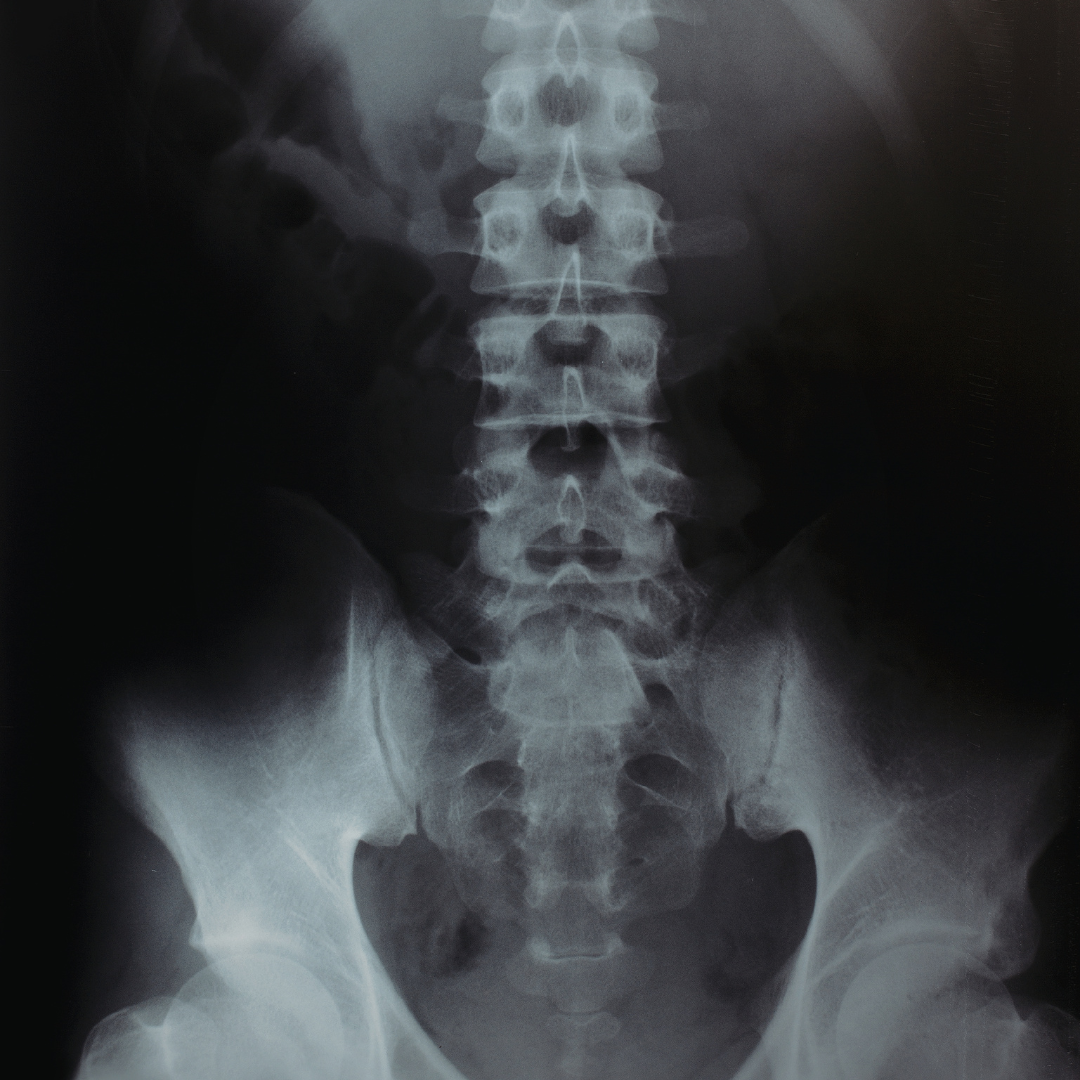

Interpretarea imagisticii coloanei vertebrale și corelarea clinică

Un curs practic care te învață cum să interpretezi RMN-ul, CT-ul și radiografiile coloanei vertebrale și cum să corelezi imaginile cu tabloul clinic al pacientului.

Lecția 7 – Scolioza: structură, rotație și implicații funcționale

Lecția 9 – Instabilitatea segmentară și spondilolistezisul

Lecția 10 – Traumatismele vertebrale și fracturile